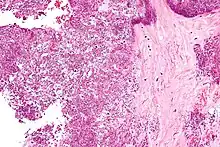

Arthrocentesis, or removing synovial fluid from the affected joint, is performed to test the synovial fluid for the calcium pyrophosphate crystals that are present in CPPD. When stained with H&E stain, calcium pyrophosphate crystals appears deeply blue ("basophilic").[16][17] However, CPP crystals are much better known for their rhomboid shape and weak positive birefringence on polarized light microscopy, and this method remains the most reliable method of identifying the crystals under the microscope.[18] However, even this method has poor sensitivity, specificity, and inter-operator agreement.[18]

Micrograph showing crystal deposition in an intervertebral disc. H&E stain.

CPPD crystals are more clearly visualized on light microscopy without a condenser.